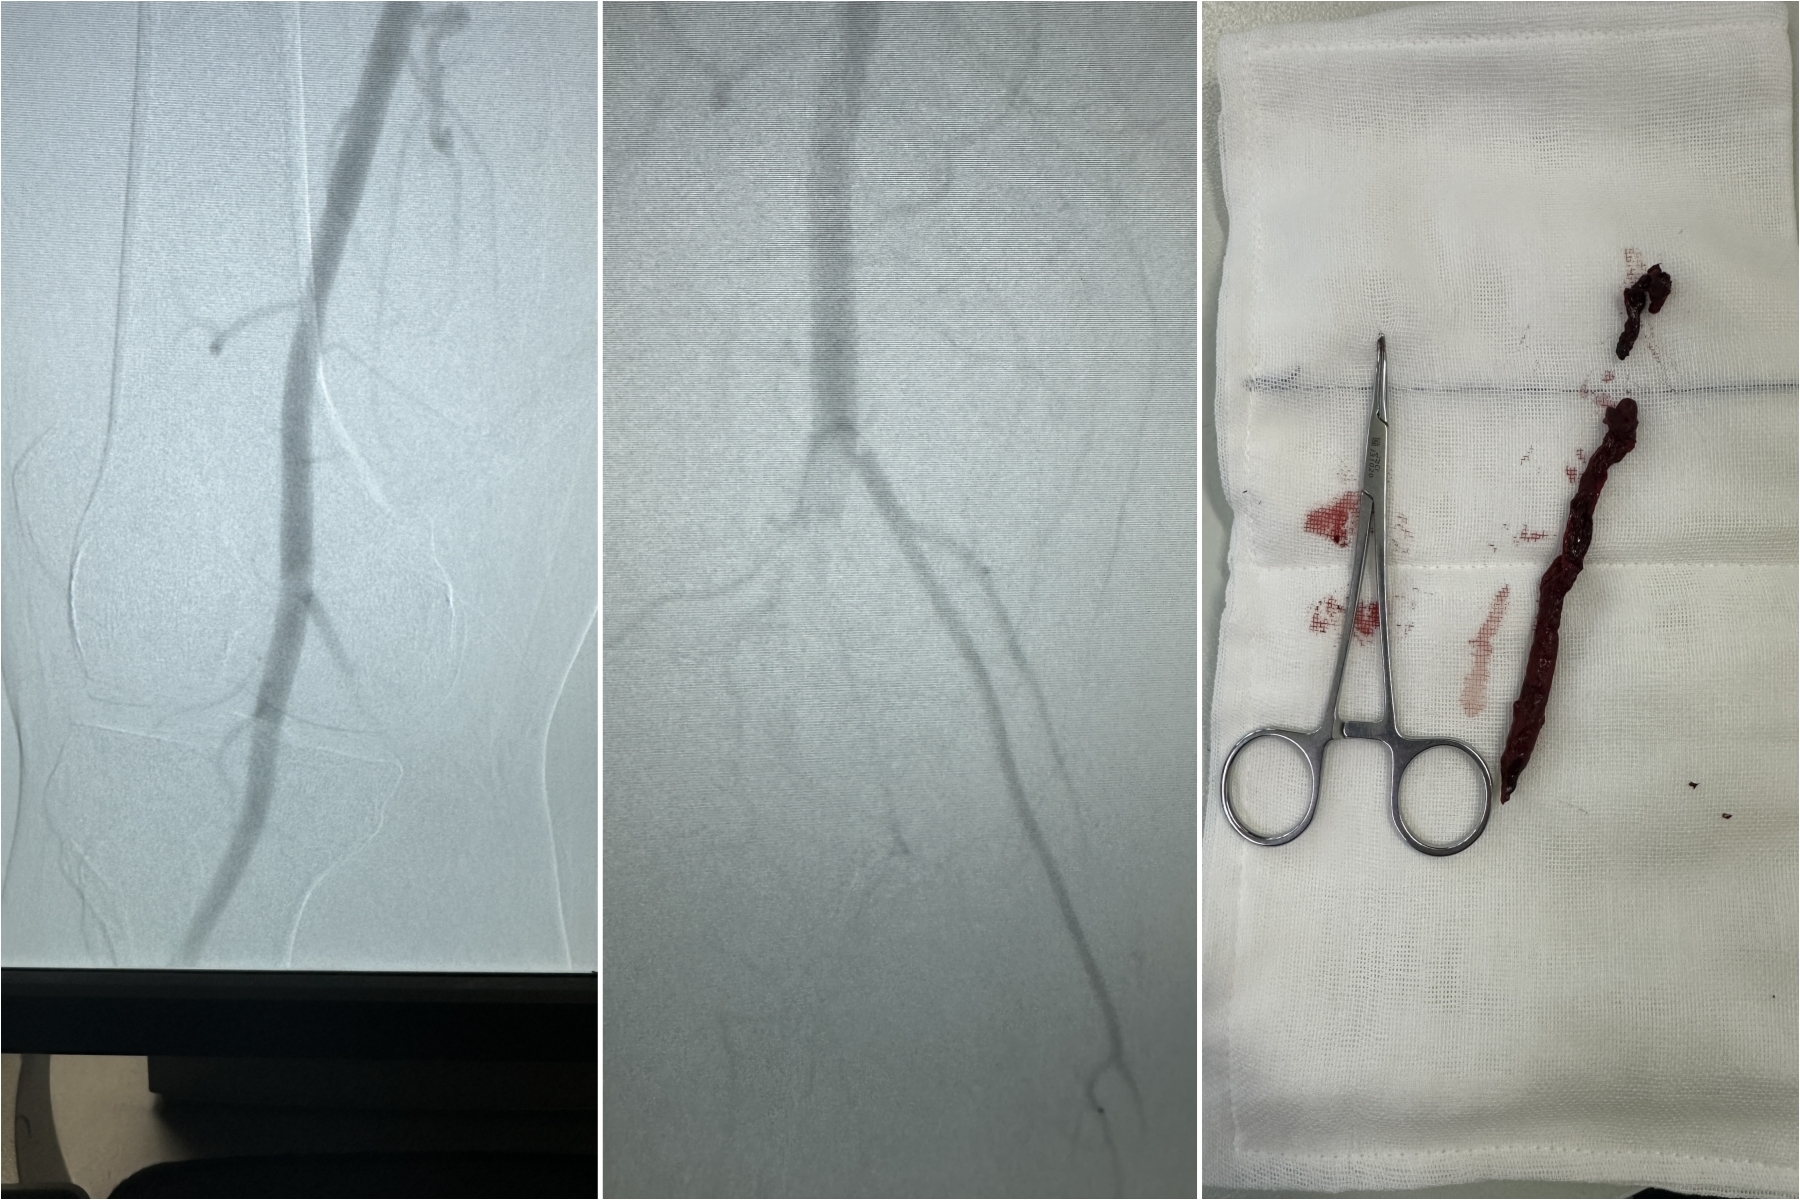

从患者右腿腘动脉,取出一长约8cm的血栓。

“不排除术前髂动脉血栓掉入腘动脉可能。”次日吴龙教授查房时,发现廖先生右下肢股动脉搏动有力,大腿皮肤温暖,但膝关节以下皮温偏低,足背动脉搏动弱,床边外周动脉超声检查高度怀疑腘动脉血栓。

“再多做一些努力。”吴龙教授协调将廖先生进入DSA手术室,并请血管外科李沁教授会诊……术中,从廖先生右腿腘动脉,取出一长约8cm的血栓,右脚皮肤温度立即转暖,足背动脉搏动触及,顺利保住右下肢。